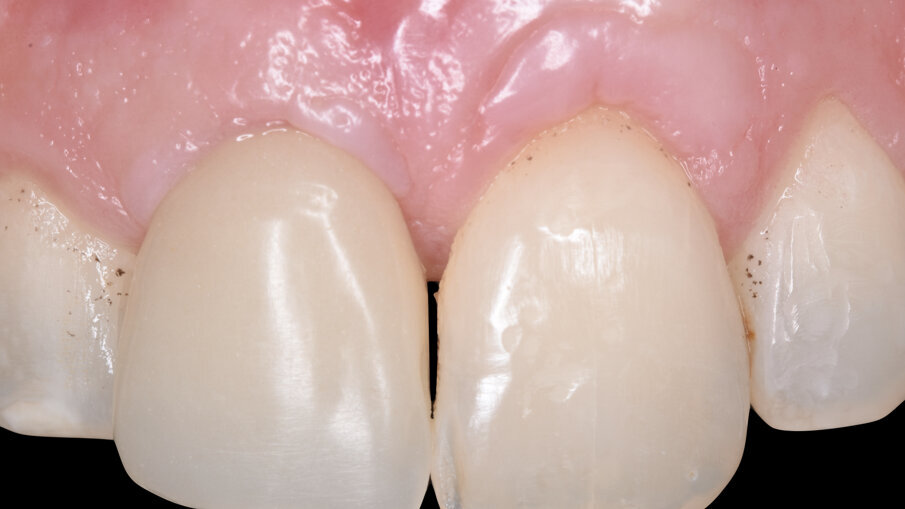

A distanza di 4 mesi dalla chirurgia implantare abbiamo ottenuto sul piano frontale un ottimo livellamento delle parabole gengivali con il ripristino di un’anatomia corretta e ideale sia dei margini gengivali di 1.1 e 2.1 sia delle papille interdentali mesiali e distali alla corona sull’impianto dell’1.1 (Fig. 15), mentre la rimozione del provvisorio avvitato ha permesso di evidenziare sul piano trasversale il condizionamento dei tessuti molli, la perfetta integrazione della matrice Fibro-Gide (Geistlich Pharma AG, Wolhusen, Switzerland) e la vascolarizzazione del sito con fibre circonferenziali ripristinando la corretta ideale anatomia attorno a un corona su impianto dal centro verso la periferia con epitelio connettivale, epitelio giunzione e epitelio sulculare (Figg. 16, 17); il nuovo livello di frequenza di risonanza è salito fino a 81 ISQ.

Dopo una prova estetica del colore e della tessitura superficiale, e un controllo radiografico bidimensionale, il caso è stato finalizzato posizionando il restauro in ceramica avvitato che è stato serrato con torque di 25 N /cm (Fig. 19). Si è ottenuto un mimetismo ideale e completamente naturale sia per quanto riguarda la componente bianca del restauro (ceramica) sia per la componente rosa (profilo, spessore e anatomia dei tessuti molli) risultando in un’estetica eccellente (Figg. 20-24).